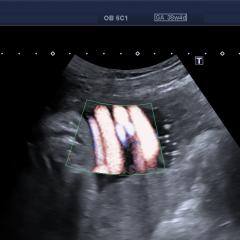

@diagnóstico 96